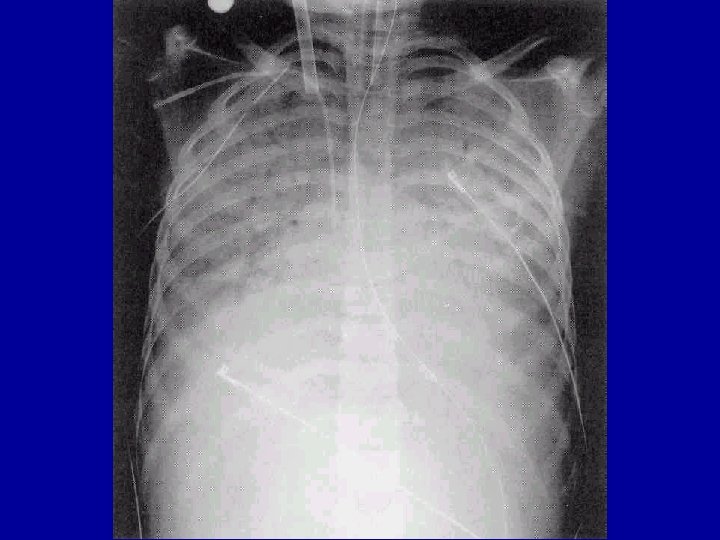

Other Laboratory Findings in ARF CXR Abnormalities Complete Blood Count (look at WBC and Hgb, which may suggest chronic hypoxia) Electrolyte Abnormalities (look at bicarbonate)

ARDS (Bilateral Infiltrates)

Flail Chest